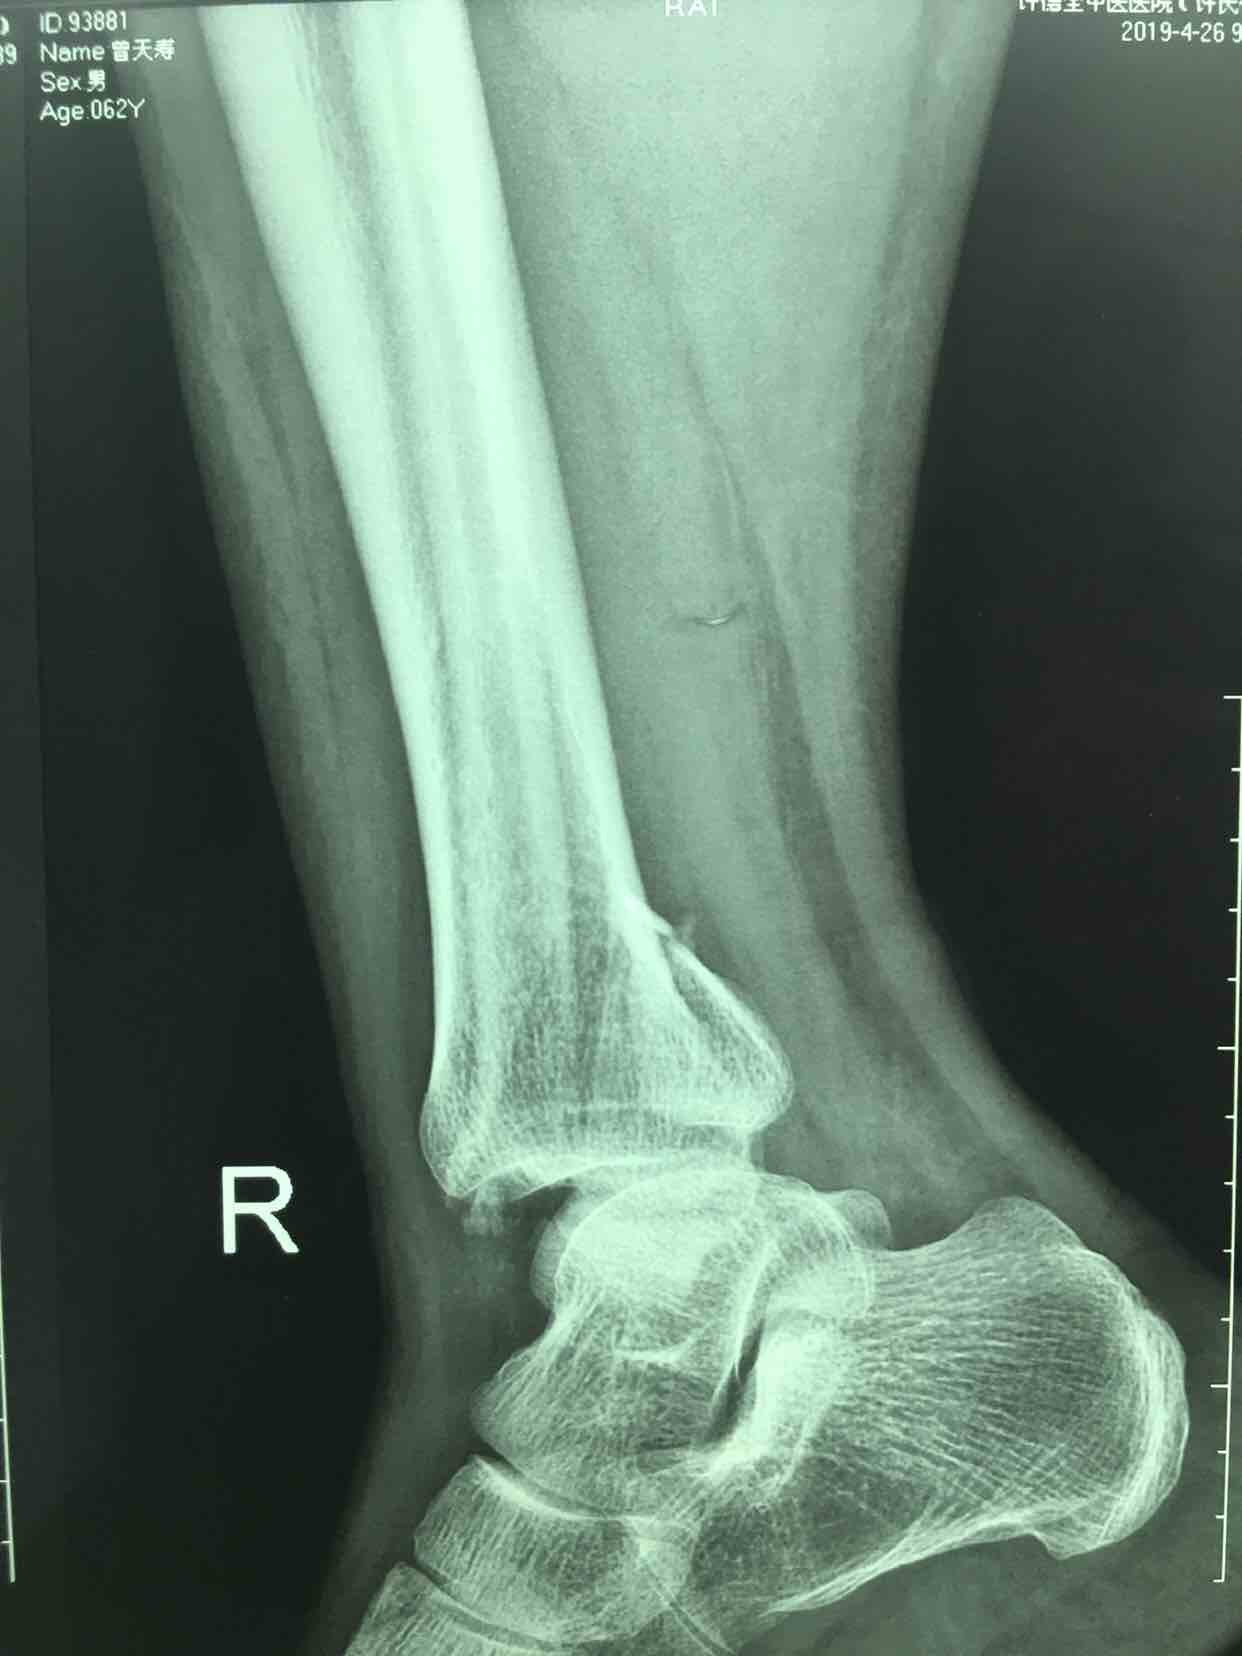

三踝骨折并胫距关节脱位(切复内固定术)

摔伤后右踝肿痛,畸形,活动受限1小时入院。既往身体健康,无特殊不良嗜好。

生命体征平稳,心肺复未见异常。右踝部肿胀,局部皮色发红,皮温高,畸形,压痛及纵叩痛阳性,可及骨擦音或骨擦感,踝关节活动受限,末梢血运感觉正常。

诊断三踝骨折并胫距关节脱位完善术前检查,待肿胀消退后在腰麻下行切复内固定术,术后石膏托固定,抗炎,消肿等处理。